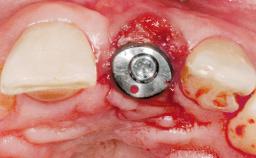

A 30-year-old female patient had lost tooth 21 and was referred to our clinic for consultation and treatment. Due to advanced apical infection, tooth 21 had been extracted two months earlier at another clinic and an acrylic-resin tooth had been bonded to the adjacent teeth. The patient desired implant treatment to avoid any damage to the adjacent natural teeth. While the patient had no history of any systemic disorder, she was a heavy smoker and exhibited medium to advanced periodontitis in the entire jaw. After the initial treatment to achieve a pocket probing depth of less than 4 mm and no bleeding on probing, a decrease in the height of the papillae mesial and distal to the extraction site and overall gingival recession were observed.

Type of Implants One-Piece|Reduced-Diameter

Placement Protocol Early or late implant placement

Loading Protocol Conventional or early

Retention Cemented, with meso-structure Cemented, with meso-structure

Provisional Implant-Supported Prosthesis Prosthodontic margin < 3 mm apical to mucosal margin Prosthodontic margin < 3 mm apical to mucosal margin